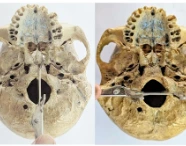

Postpartum Haemorrhage: A Case Series Highlighting Diverse Clinical Profiles and Evolving Management Strategies in a Tertiary Care Setting